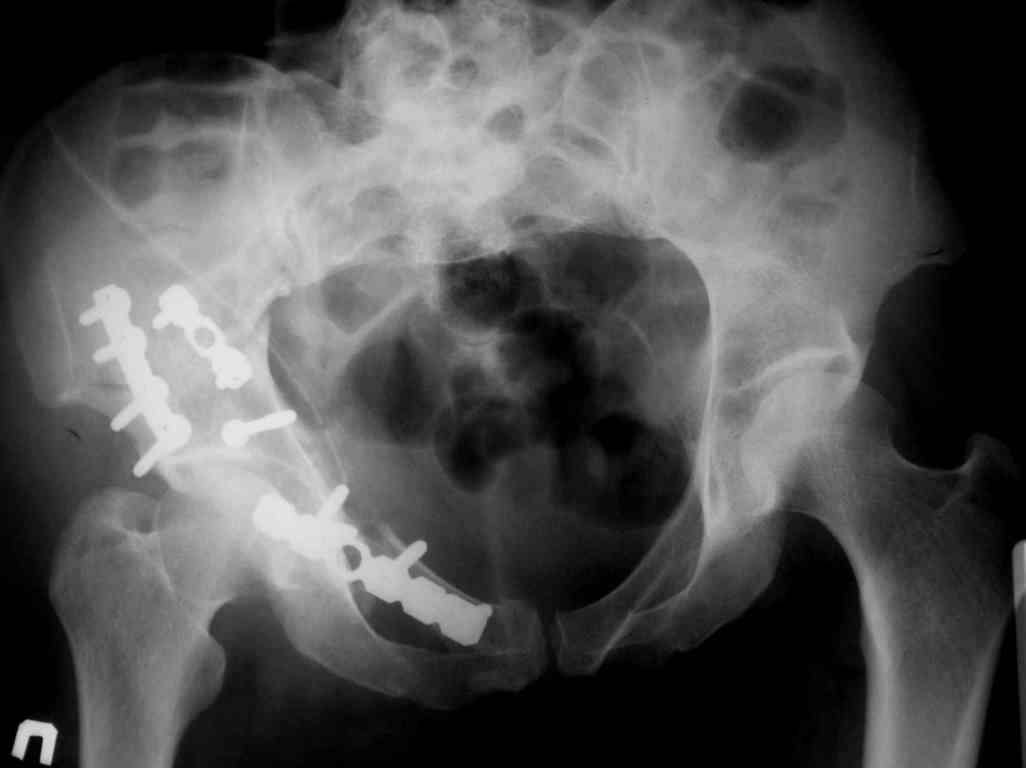

Re: acetabular fracture

послал Михаил Марикин 19 Сентябрь 2006, 08:33

У нас есть не большой опыт в лечении подобных больных. Не большой, поскольку к счастью поступают они не часто. Используем подвздошнопаховый доступ хорошо описаный у Мюллера. Манипуляция полностью обработанной ногой на стороне перелома помогает в репозиции и мобилизации сосудов и мышцы вместе с бедренным нервом. Доступ удобный, но требует аккуратности (надо помнить о венах тазового дна). Кроме того до операции делаем 3D реконструкцию. Это позволяет рассмотреть перелом во всей красе и спланировать ход операции.